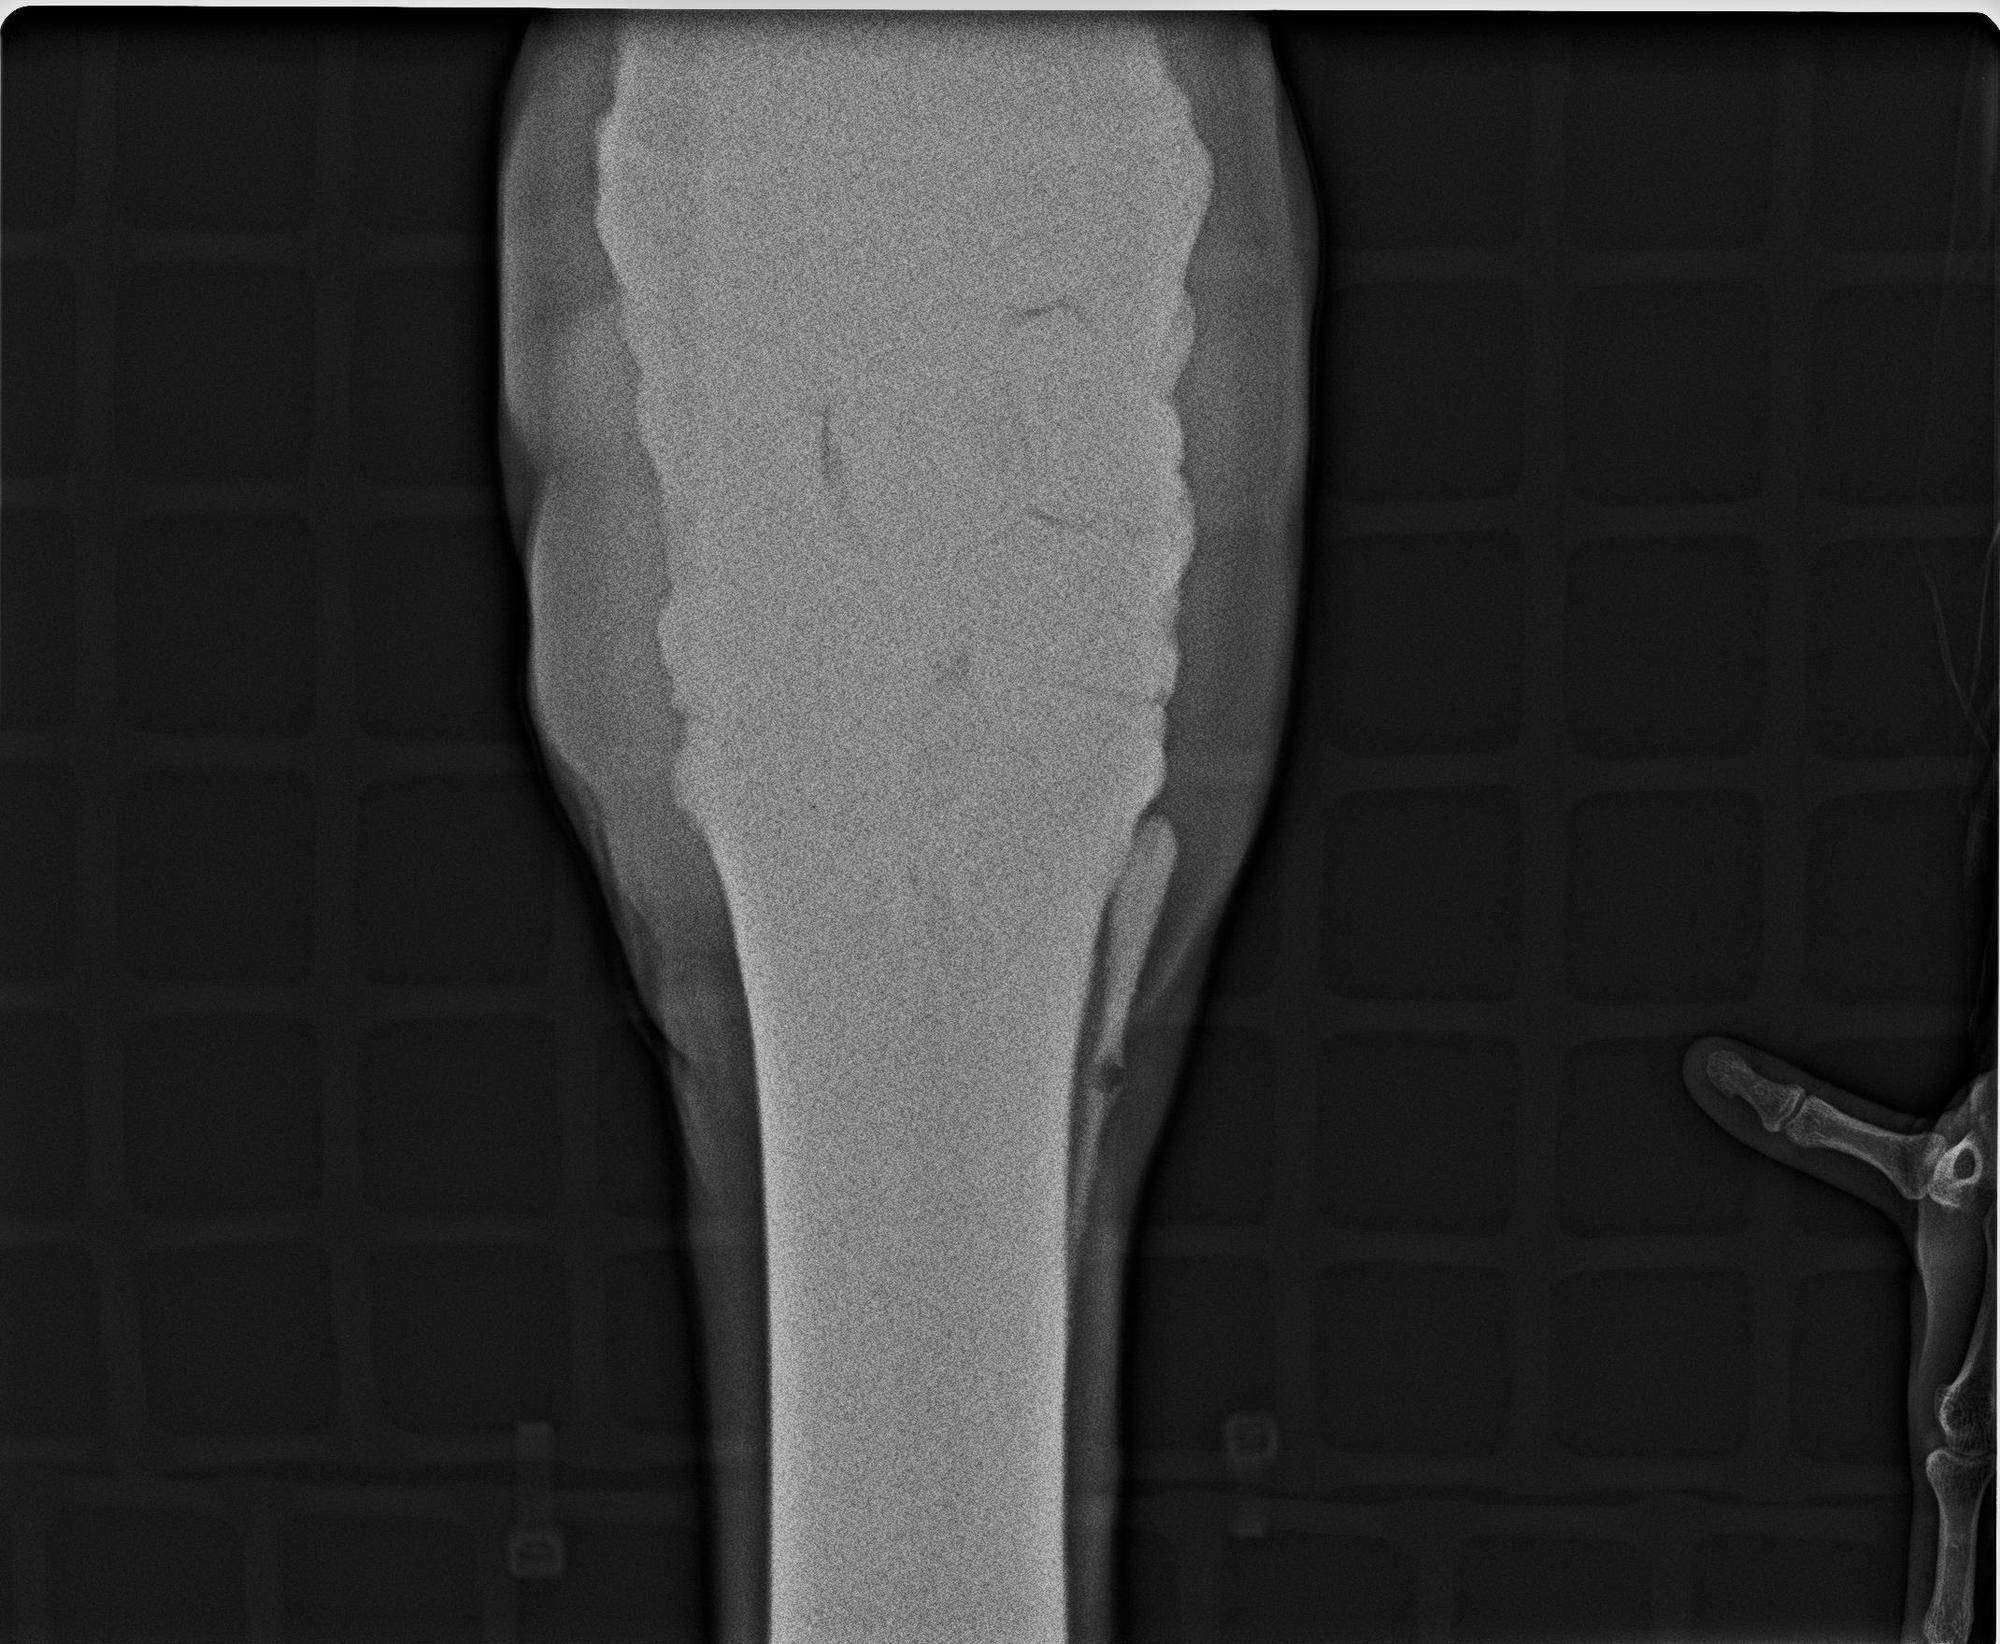

これはキリンの「そら」の左前肢の前膝のレントゲン写真です!

結果は・・・最初の写真の通り無事に撮影することができました!!

撮影する部位も前後左右、前膝や球節、蹄などたくさんあります。